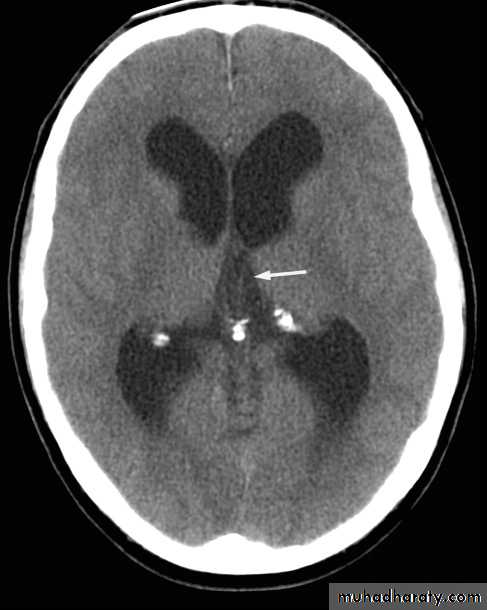

• Pineal

• Choroid plexuses• Dura (falx; tentorium; over vault)

• Basal ganglia and dentate nuclei

• Pituitary gland

• Lens

Normal intracranial calcification